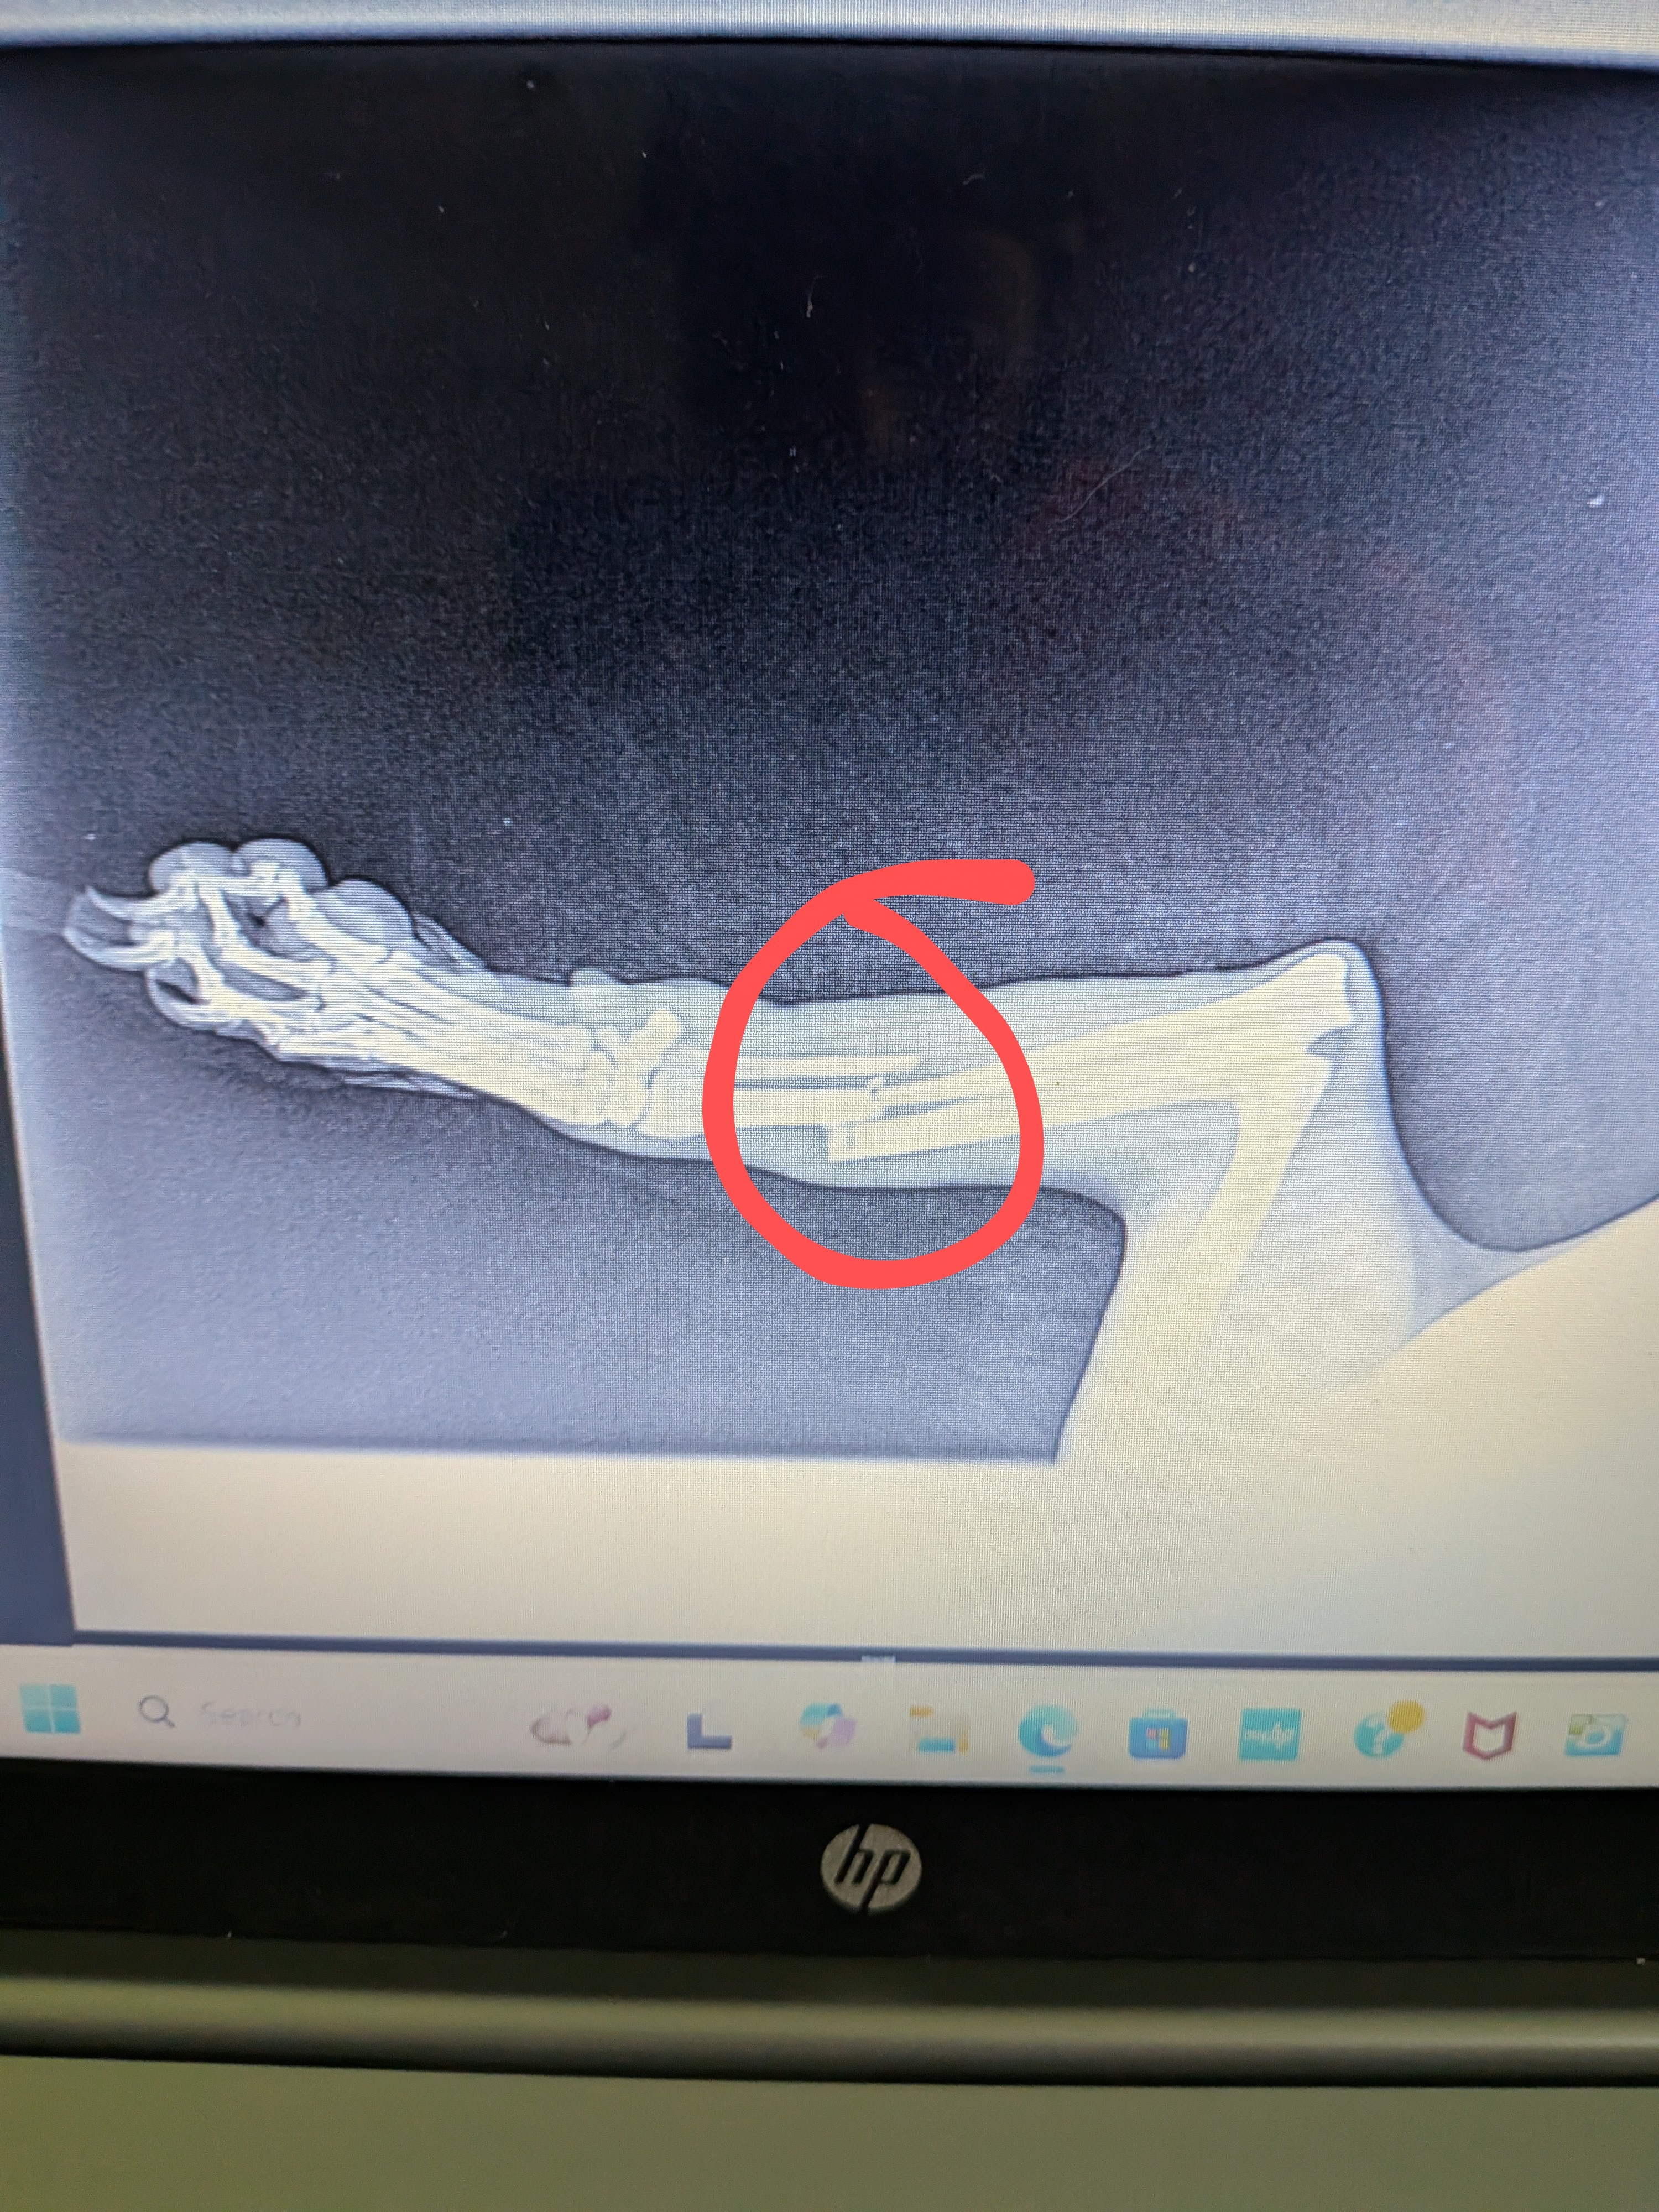

Hello, my name is Will. On Thursday, May 29th, while I was at work, I got a text from my daughter's grandma saying that when she came by to give Lady a treat, she noticed she was limping and thought that her leg was broken! So, immediately after I got off work, I rushed to see what was going on. Sure enough, Lady wasn't running up to me as she normally does. Her right front leg was completely limp, and she limped towards me in obvious pain. I inspected it as well as I could and knew then it was a break or a sprain. So, the next morning, I got a vet appointment for 1:30 to get her in and get X-rays done.

- Sure enough, it was a clean break. The veterinarian informed me that she would have to get surgery to have the bone placed right ASAP. Due to financial hardships recently, I just can't afford to get it done. So, I'm reaching out for any help possible. I've had Lady since she was 3 months old; she's 10 years old now. She's been the best dog anyone can ask for, and my kids absolutely love her! I've never done a GoFundMe or anything like this. I'm just in a bind right now and looking for any help I can get. Thank you.